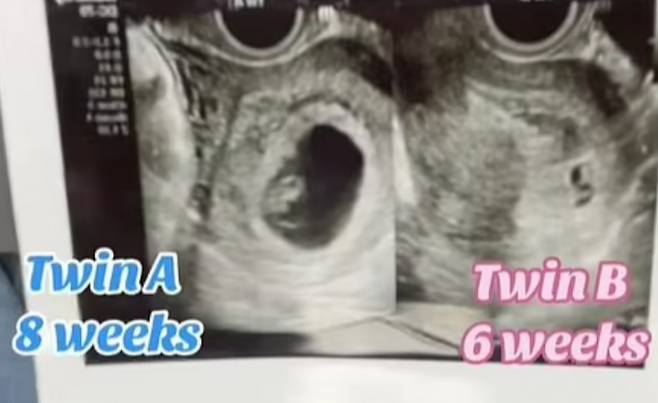

지난 19일(이하 현지시각) 데일리메일에 따르면 미국 텍사스에 거주하는 테일러 헨더슨(28)은 임신 8주 차에 두 명의 아이를 임신한 사실을 확인했다. 헨더슨은 "산부인과에서 초음파 검사를 받았는데 두 명의 태아가 있는 것을 발견했다"며 "이들은 쌍둥이가 아니었다"고 말했다.

그는 "한 태아는 8주 전에 임신이 됐고 다른 태아는 6주 전에 임신이 된 거였다"며 "딸을 가진 후에 성관계를 가졌는데 그때 임신이 된 것 같다"고 밝혔다.

헨더슨은 '중복 임신' 진단을 받았다. 중복 임신은 임신 중 또 한 번 임신이 되는 것으로 동일한 배란기에 난자가 복수로 수정되는 것을 뜻한다. 그의 의료진은 "중복 임신 확률은 거의 0에 가깝다"며 "전 세계적으로도 10여 건에 불과하다"고 전했다.